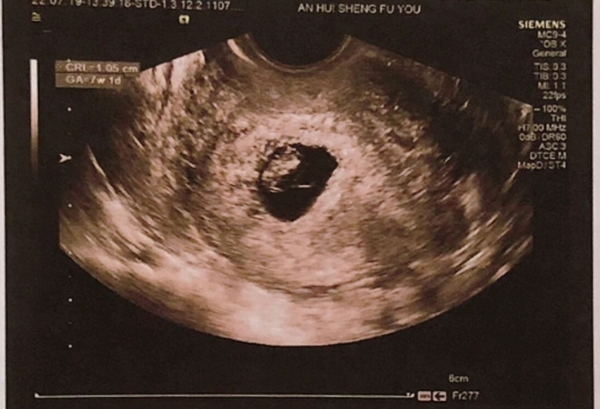

根据临床数据,怀孕7周时孕囊的平均直径通常在15-25毫米之间,呈圆形或椭圆形。此时超声检查应可见卵黄囊及原始心管搏动,这是胚胎健康发育的重要标。

个体差异:孕囊大小受月经周期、受精卵着床时间等因素影响。例如,排卵延迟的孕妇孕囊可能偏小,但若日均增长约1毫米且胎心正常,仍属合理范围。

异常警示:若孕囊直径小于15毫米且无胎芽,需警惕胚胎停育;超过25毫米未见胎芽则可能为空孕囊,需结合血HCG等检查综合判断。